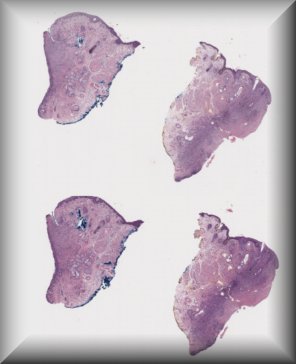

Steffen Heegaard (Copenhagen): Ligneous conjunctivitis in a 12-year-old Turkish girl |